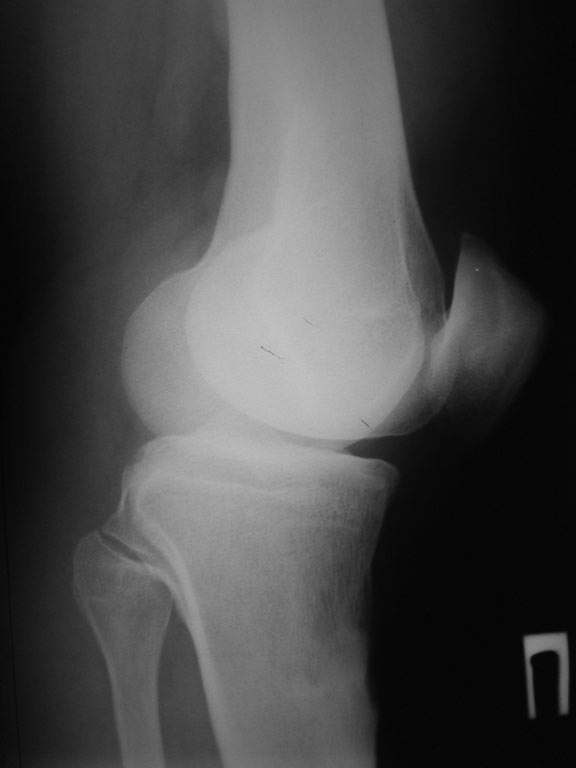

Пациент наконец то объявился вновь, и мы смогли выполнить новые снимки как лежа, так и в нагрузке.